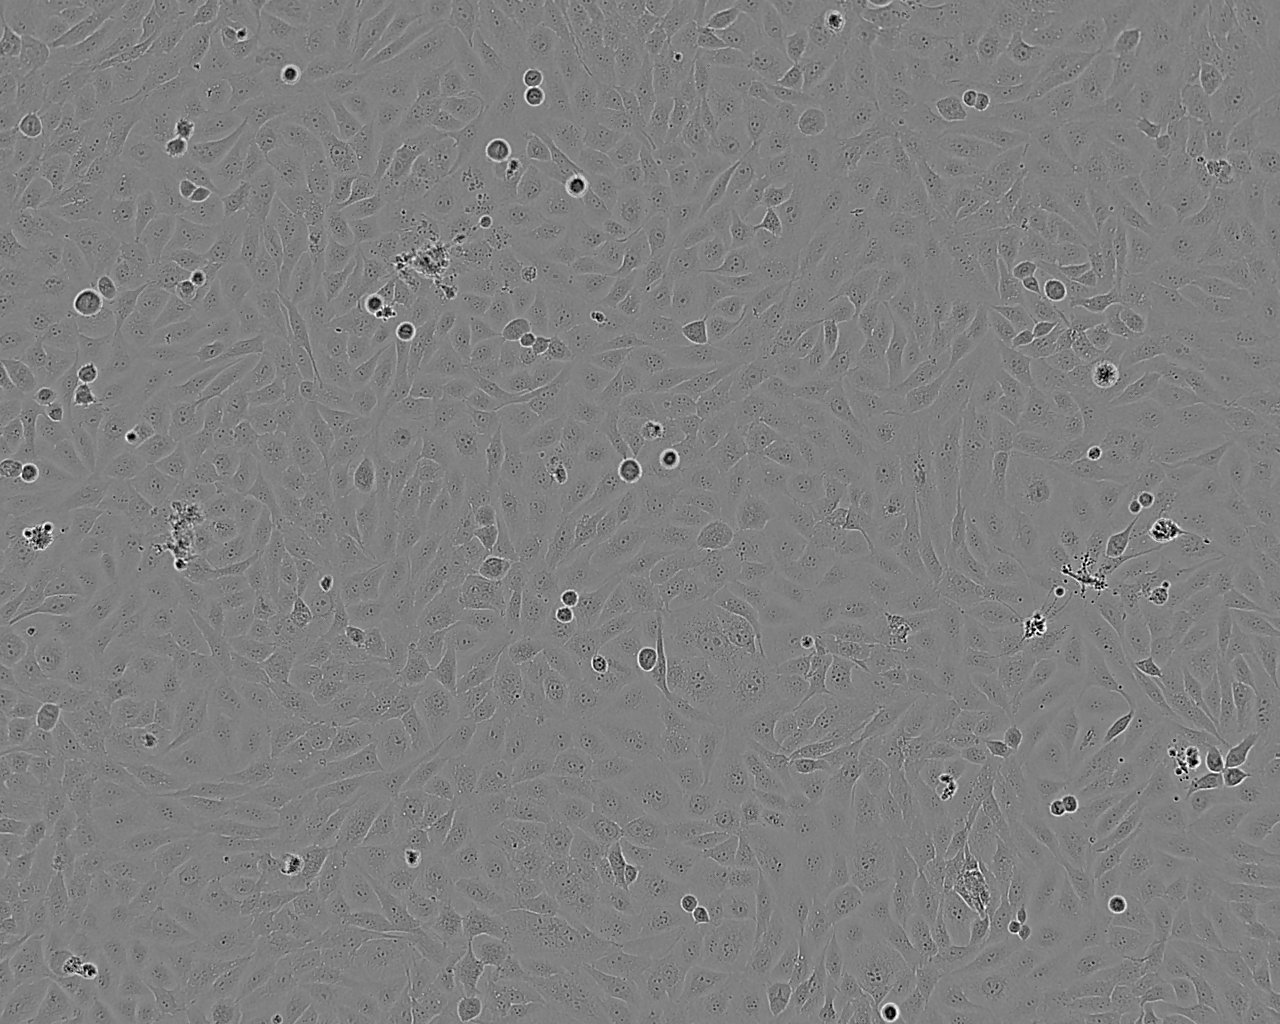

细胞形态:上皮细胞样

细胞生长:贴壁

细胞生长特性:贴壁